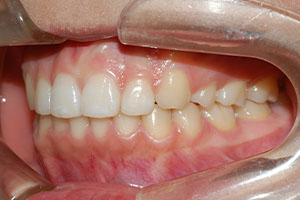

치료증례 전후사진

Before & After